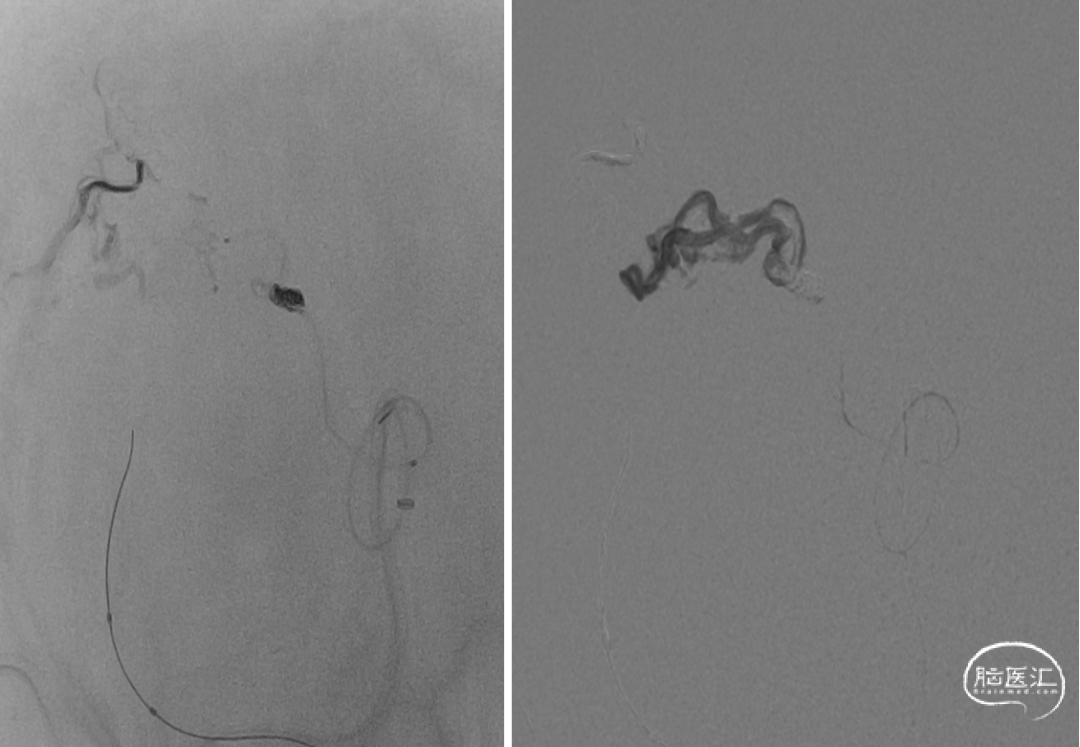

静脉入路超选

供血动脉球囊保护;静脉压力锅技术,onyx18栓塞

术后即刻造影血管畸形消失